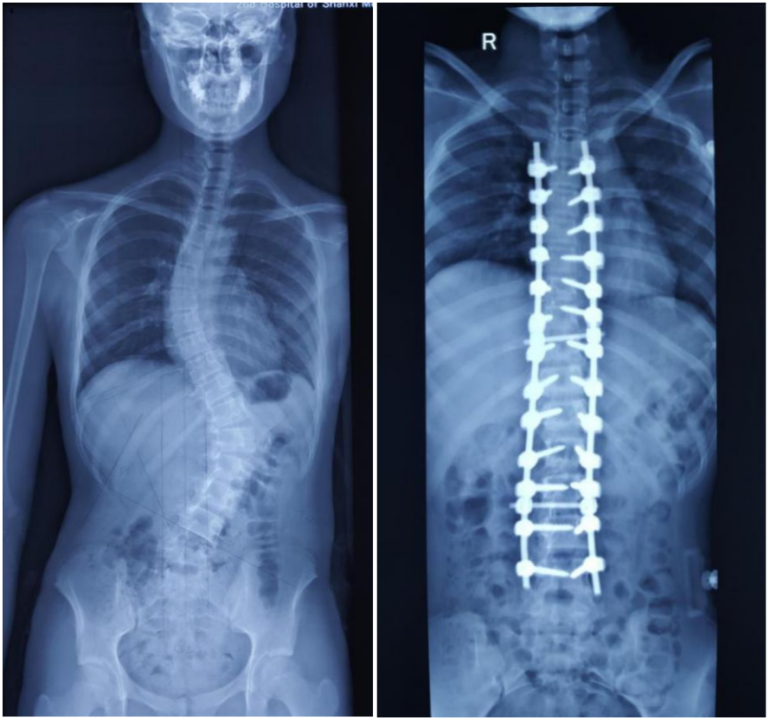

手術(shù)治療(適用于重度側(cè)彎)

圖示:脊柱側(cè)彎術(shù)后前后對(duì)比

● 條件:側(cè)彎角度大于40-50度,并且有持續(xù)加重的趨勢(shì)。

● 方法:通過(guò)外科手術(shù)進(jìn)行脊柱矯形融合。簡(jiǎn)單來(lái)說(shuō),就是用特制的金屬釘棒系統(tǒng)將彎曲的脊柱矯正到盡可能直的位置,并通過(guò)植入的骨頭(自體骨或異體骨)讓需要固定的脊柱節(jié)段最終長(zhǎng)成一個(gè)整體。手術(shù)的主要目的是阻止側(cè)彎進(jìn)一步惡化,避免其對(duì)心肺功能造成影響,并改善外觀。